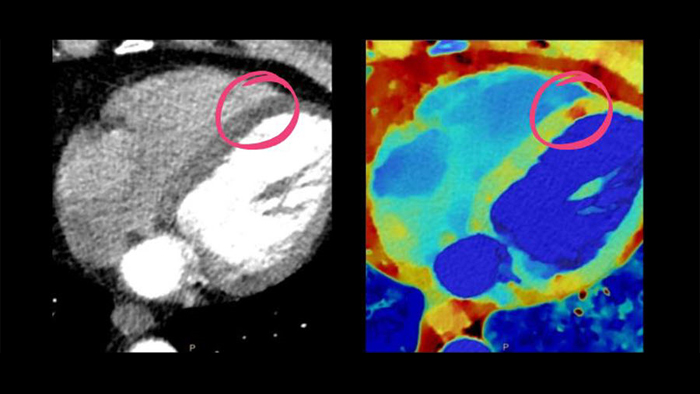

Erhöhte Diagnosesicherheit dank Spektral-Detektor-CT. Mit Hilfe von Zeff Karten konnte die Minderperfusion der LCX eindeutig diagnostiziert werden.